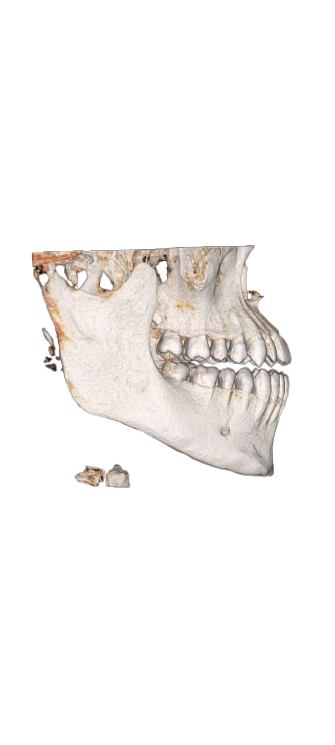

My maxillofacial surgeon said there are no problems and the solution depends on the bite and teeth

Screenshot_2026-03-12-20-45-14-649_com.openai.chatgpt-removebg-preview.png115.2 KB · Views: 0

Screenshot_2026-03-12-20-45-14-649_com.openai.chatgpt-removebg-preview.png115.2 KB · Views: 0 -